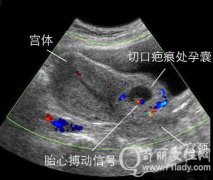

什么是瘢痕妊娠?单独二胎申请者30-39岁需警惕瘢痕妊娠